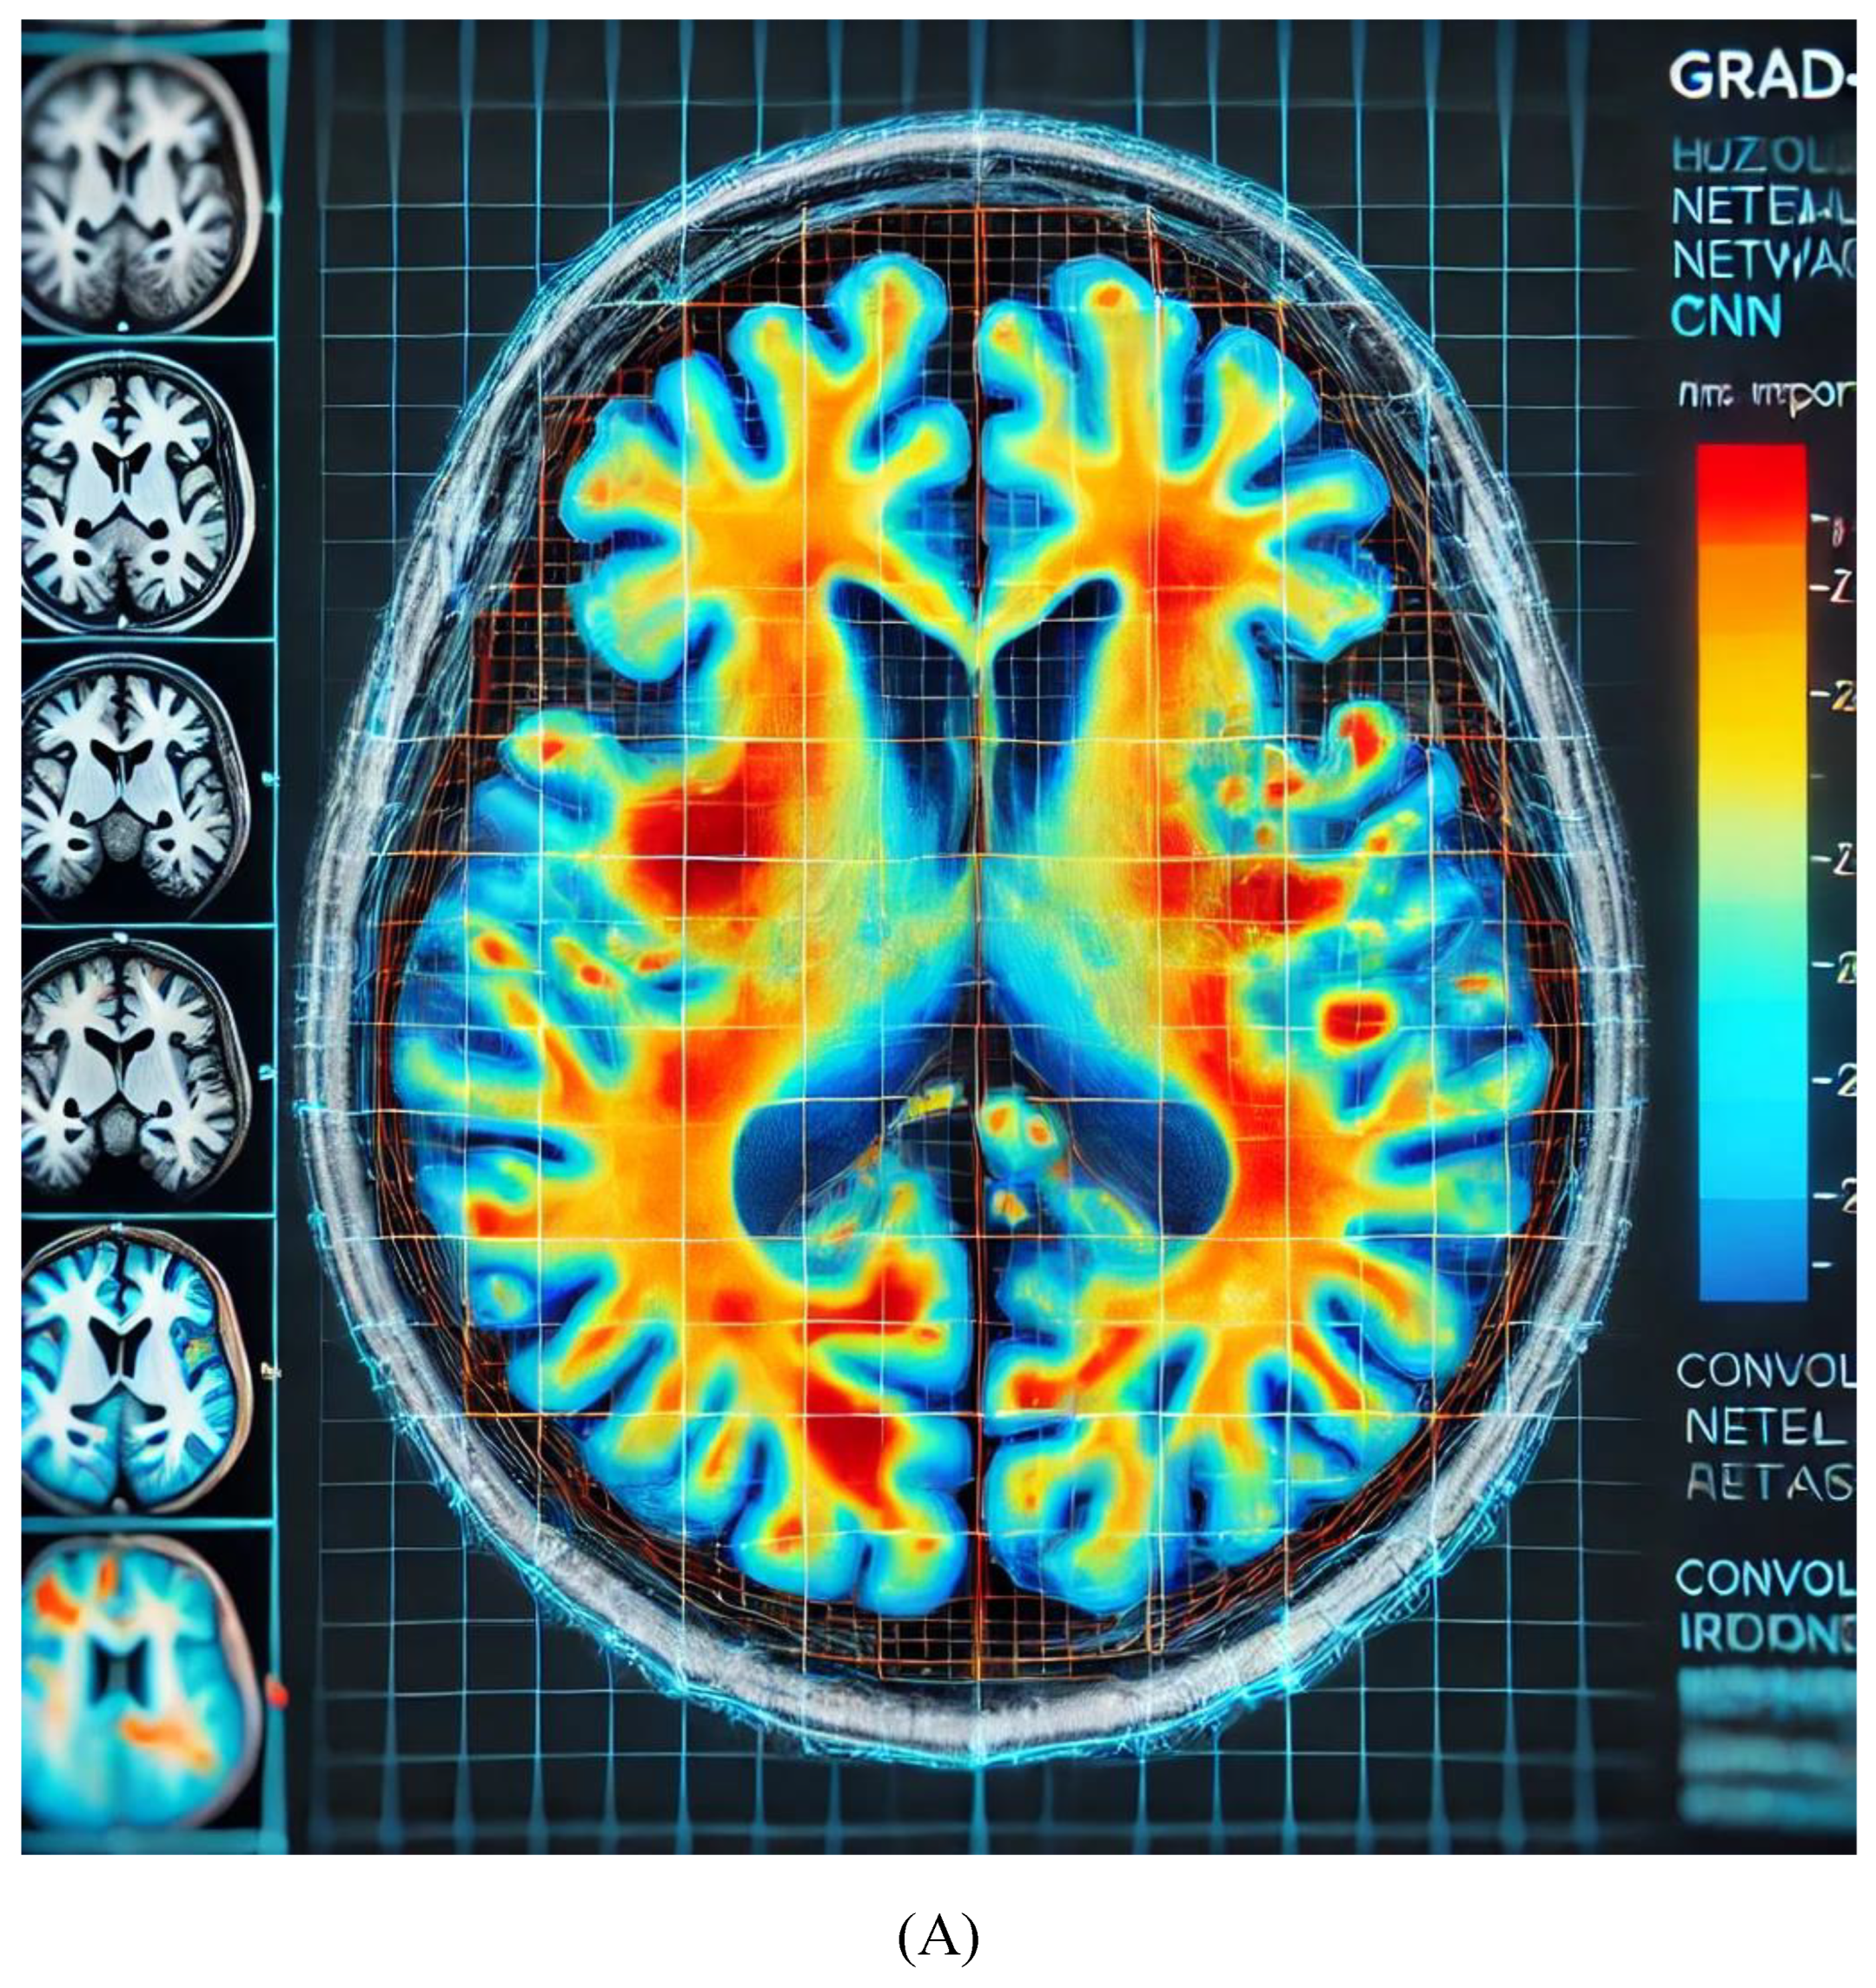

Grad-CAM is a widely used method to provide visual explanations for CNNs in medical imaging. By applying Grad-CAM, clinicians can see the regions of medical images that the model has focused on when making a diagnostic decision [70]. As shown in Figure 1, the heatmap highlights the areas of importance in a brain MRI for detecting a tumor.

Grad-CAM: Grad-CAM is particularly useful in medical imaging, where it overlays heatmaps on input images to visualize which regions most influence the CNN’s decision [95]. For example, it can highlight tumor regions in MRI and CT scans, making the CNN’s reasoning transparent [96,97,98].

The heatmap in Figure 3A highlights areas of importance in the brain MRI, where red/orange regions indicate higher relevance in the CNN’s decision-making process for diagnosing Alzheimer's. This helps clinicians confirm whether the AI model is focusing on clinically significant regions, improving the transparency of AI predictions. Figure 3B illustrates a Decision Tree for breast cancer treatment recommendation, with nodes representing key features such as tumor size, hormone receptor status, HER2 status, and patient age. Each branch leads to a treatment recommendation (chemotherapy, hormonal therapy, or targeted therapy), showing how the AI model arrives at personalized decisions based on clinical and genetic factors. This decision tree is a visual representation of how explainable AI models in oncology provide clear, interpretable pathways for treatment recommendations, making them transparent for clinicians. Figure 3C illustrates SHAP values for heart failure readmission prediction, showing the impact of three critical features: age, blood pressure, and previous hospitalizations. Each dot represents a patient, with the position on the x-axis indicating the feature values and the y-axis showing the SHAP values, which measure the contribution of each feature to the model's prediction. Positive SHAP values indicate a higher likelihood of readmission, while negative values suggest a lower likelihood. This visualization helps clinicians focus on key risk factors and offers transparency in AI predictions for better decision-making. Figure 3D illustrates the Attention Mechanism in NLP for EHR analysis, where the heatmap highlights relevant words in a patient's electronic health record (EHR). This mechanism helps the AI model focus on key terms such as "diabetes" and "blood pressure," which are crucial for making predictions about patient health. The attention scores provide transparency, allowing clinicians to understand which parts of the EHR the model considered most important.